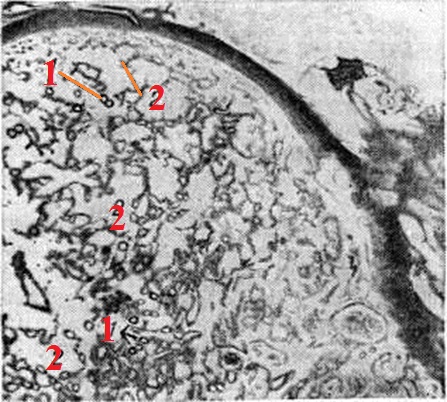

Патогистология: разрастания грануляционной ткани с большим количеством расширенных с набухшим эндотелием капилляров (рисунок 1), строма отёчна, иногда содержит воспалительный инфильтрат, состоящий из лимфоцитов, тучных клеток, в более поздних стадиях — из фибробластов.

Рис. 1.

Микроскопическая картина гранулемы пиогенной: выражены многочисленные капилляры (1) и венулы (2) среди рыхлой соединительной ткани.